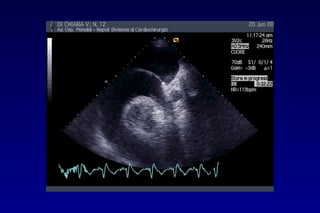

METODOLOGIA DI STUDIO

L’accumulo di quantità

maggiori di liquido

determina l’estensione

dello spazio eco-privo

lungo il bordo laterale

del cuore e

anteriormente

fino a circondare

completamente le

cavità cardiache

Uno studio completo del pericardio richiede diversi

approcci: parasternale asse lungo e asse corto,

apicale, sottocostale.